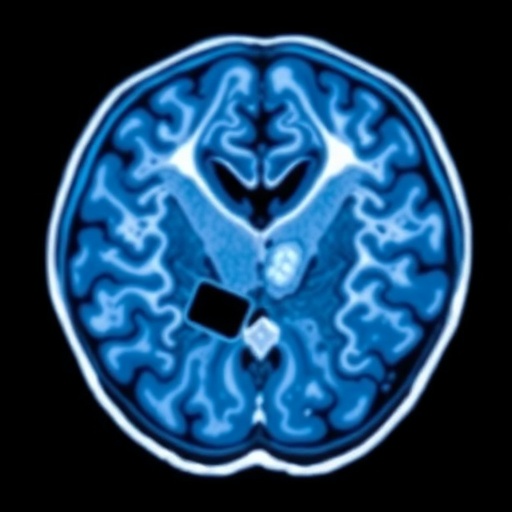

Intracranial hemorrhage is a serious medical emergency that can lead to significant morbidity and mortality if not diagnosed and treated quickly. Traditionally, diagnosing ICH has relied heavily on expert radiologists interpreting CT scans. However, this study explores the possibility of enhancing diagnostics through AI, which can analyze vast amounts of imaging data much faster than a human alone. This research aims to determine whether AI, trained predominantly on adult data, can maintain reliability when applied to a younger age group.

The researchers employed a comprehensive methodology. They utilized a state-of-the-art AI algorithm, specifically engineered for ICH detection, and validated it against a large dataset of head CT scans from children. These scans were sourced from diverse clinical settings to ensure a comprehensive evaluation. Notably, the age range of participants ensured a robust analysis of AI responsiveness in varying pediatric demographics. By examining various scenarios and conditions, the study aimed to establish an accurate measure of the AI model’s diagnostic capability, ensuring that it functions effectively across the board.

Initial findings of the study reveal that the AI tool demonstrated a commendable level of accuracy in detecting ICH in the pediatric cohort, suggesting that it could serve as an additional asset in clinical decision-making processes. While the AI performed exceptionally well in identifying clear cases of hemorrhage, the research also identified scenarios where the model faced challenges. Particularly, subtle cases of ICH that might be easily overlooked by human eyes were highlighted as a key area for the AI’s development. These findings underscore the ongoing need for refinement and retraining of AI systems with diverse and representative pediatric datasets.